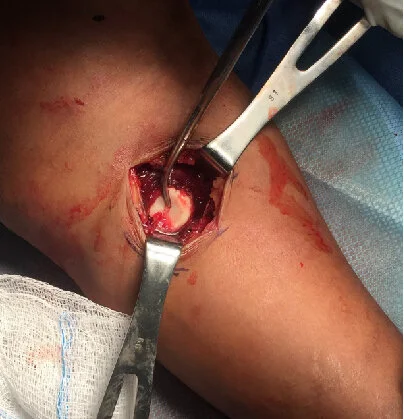

Surgery was performed with the patient supine using the ElbowLOC® Arm Positioning System. A standard posterolateral approach was performed. Both collateral ligaments had been stripped off the humerus. The proximal ulna including the coronoid was intact. The brachialis insertion was shredded along with much of the proximal forearm musculature. The radial head was faintly palpable anterior and medial to the ulna but could not be visualized. The median and anterior interosseous nerves could easily be seen from the posterior approach. I removed the radial head through an anteromedial incision, with the arm extended on our radiolucent hand table as shown below. I inserted a radial head implant and repaired the lateral collateral ligament and lateral soft tissue envelope. The elbow was stable to full extension at this point, so the ulnar collateral ligament was not surgically repaired. At her one week post op visit, a hinged elbow splint with a 30 degree extension block was applied, and she was referred for supervised hand therapy. Below are radiographs taken 4 weeks post op, where she had full forearm rotation, extension to 20 degrees, and 115 degrees of flexion